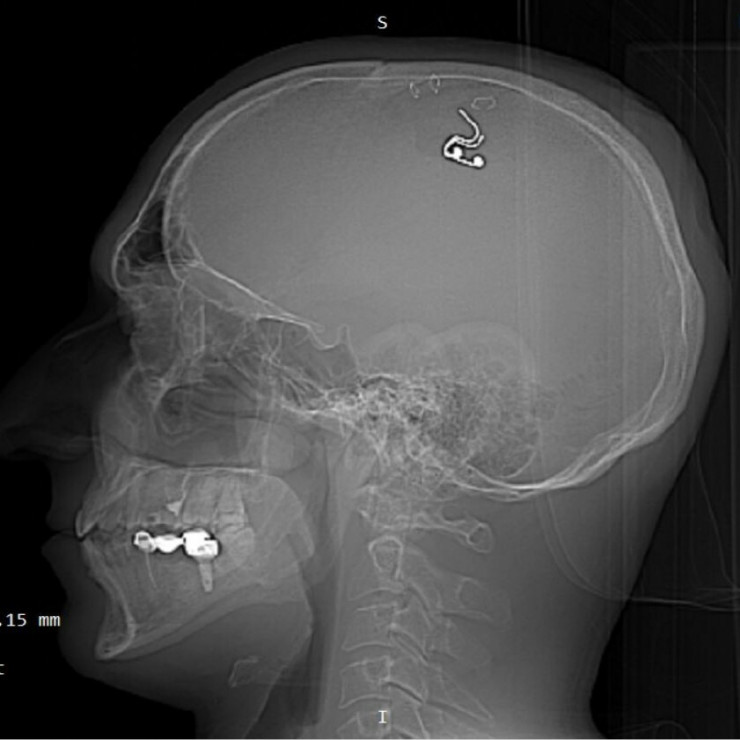

Россиянин Михаил Радуга, который просверлил себе череп в Алматы, рассказал о своем состоянии, а также высказался об исследовании компании Илона Маска, которая успешно вживила чип в мозг человека, передает корреспондент Tengrinews.kz.

В июле прошлого года Михаил просверлил себе череп с помощью дрели и вставил себе в мозг, сделав трепанацию, электрод. Россиянин объяснил, что целью такого опасного поступка стала электрическая стимуляция моторной коры мозга, чтобы исследовать осознанные сны. После пяти недель "исследований" он удалил электроды в одной из частных клиник Алматы.

Корреспондент Tengrinews.kz связался с Михаилом и узнал, как он чувствует себя сейчас. По словам мужчины, чувствует он себя отлично: активно тренируется и не испытывает никаких проблем. В черепе у Михаила осталось небольшое отверстие.

"После операции нет побочных эффектов, первые два месяца я чувствовал перепады в давлении, когда наклонялся, потом это прошло. Иногда, когда кашляю, чувствую, как что-то поддавливает. Когда гуляю на улице или тренируюсь, надеваю титановую бейсболку, чтобы в отверстие ничего не прилетело", - говорит Михаил.